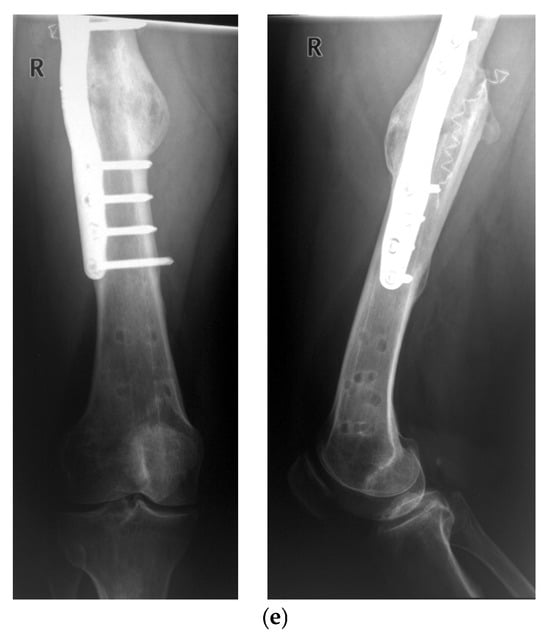

Long-Term Evaluation of Bone Healing Monitoring Using an Instrumented Plate with Measurement Sensors (Smart Implant) over 10 Years

by Arndt P. Schulz, Birgitt Kowald, Matthias Münch, Klaus Seide, Nils Weinrich, Tobias Barth and Benjamin Kienast

Sensors 2025, 25(18), 5779; https://doi.org/10.3390/s25185779 - 16 Sep 2025

A total of 66 smart implants were included. As a measure of bony stability, the relative elastic compliance of the osteosynthesis was determined from the gradient between the applied external load and the measured implant load over the entire healing process. The healing [...] Read more.

A total of 66 smart implants were included. As a measure of bony stability, the relative elastic compliance of the osteosynthesis was determined from the gradient between the applied external load and the measured implant load over the entire healing process. The healing process of non-unions of the femur with a smart implant was tracked by telemetric measurements over a timespan of up to 10 years. The measurements of the longest healing process show a very slow but constant decrease in force transmission over the implant, radiological findings over 10 years show corresponding consolidation until bony healing. The use of a telemetrically instrumented bone plate, a so-called smart implant, to monitor the healing process is a successful procedure to support the clinician in his decision to take further surgical measures or to wait until healing occurs. Full article